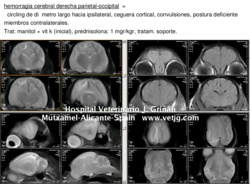

Caso clínico. Gato que nos remiten, al que se le había realizado la ovariohisterectomía pocos días antes. |

imágenes de resonancia magnética donde se demuestra la hemorragia cerebral. |